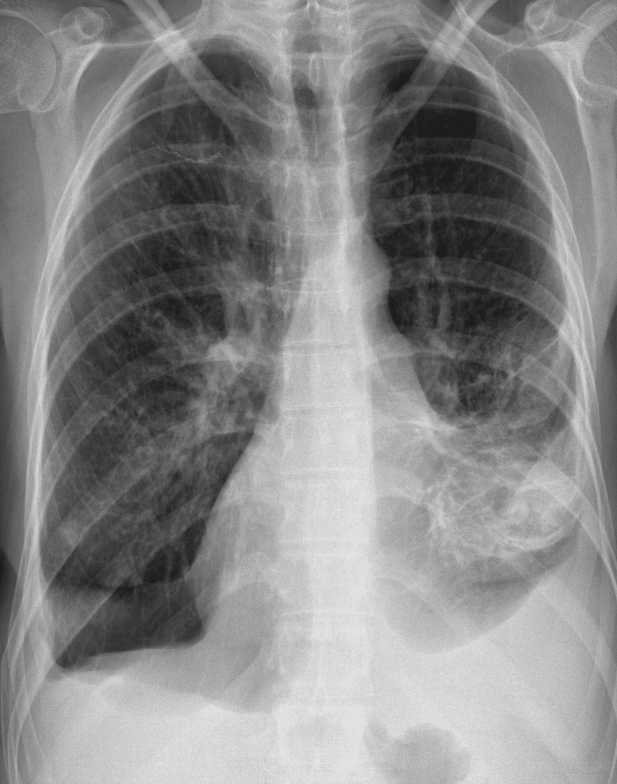

Refer to caption

(a) ”Normal”

(b) ”Bone suppressed”

(c) ”Lung field cropped”

(d) ”Combination”

Fig. 1: One example image (a) of the Indiana chest X-ray dataset from Open-I. The dataset consists of 3125 frontal and lateral images from 3125 patients. We annotated all images with up to eight findings. The pre-processed images are show in (b)-(d). (b) is the bone suppressed image, (c) is cropped to the lung field, and (d) illustrates the combination out of (b) and (c).